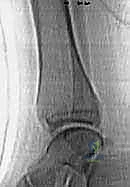

- الأشعة السينية (X-rays): هي الخطوة الأولى والأساسية. يتم التقاط صور من زوايا متعددة (أمامية، جانبية، ومائلة) لتقييم الكسر.

- الأشعة المقطعية ثلاثية الأبعاد (3D CT Scan): تُعد ضرورة حتمية في حالات كسور تيلوكس والكسور ثلاثية المستويات، أو أي كسر يمتد داخل المفصل. توفر الأشعة المقطعية خريطة دقيقة لحجم القطع العظمية ومقدار التباعد (Displacement)، مما يساعد في التخطيط الجراحي المسبق.

- التصوير بالرنين المغناطيسي (MRI): يُستخدم في حالات نادرة لتقييم إصابات الأربطة والأنسجة الرخوة المصاحبة، أو للتحقق من الإصابات الغضروفية غير المرئية في الأشعة السينية.